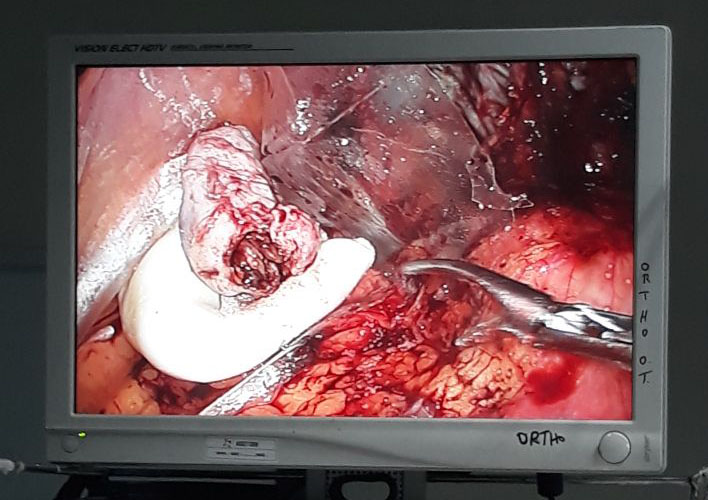

A Young lady who was a small kid...when her mother was operated for a Complex Gastrointestinal condition almost 14 years back by Dr Suddhasattwa Sen suddenly came in with severe blood loss from Gastrointestinal tract with a loss of almost 2 to 3 litres of blood with Shock with fainting . Further stabilisation was done and then extensive investigation revealed not only Piles and GI Ulcers but also SRUS Bleeding ulcers in rectum. A condition called Solitary Rectal Ulcer Syndrome ( a complex and difficult to cure anorectal problem ) . Her hemoglobin dropped to below 7 gm% She finally underwent surgery after 5 days and left home after 2 days post op without any further bleed or problems .